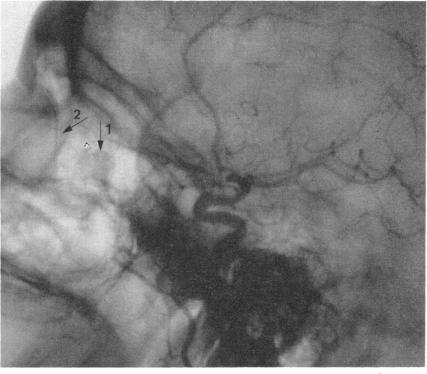

Arteriography and phlebography in the diagnosis of orbital affections.

Bull N Y Acad Med. 1968 Apr;44(4):409-30.